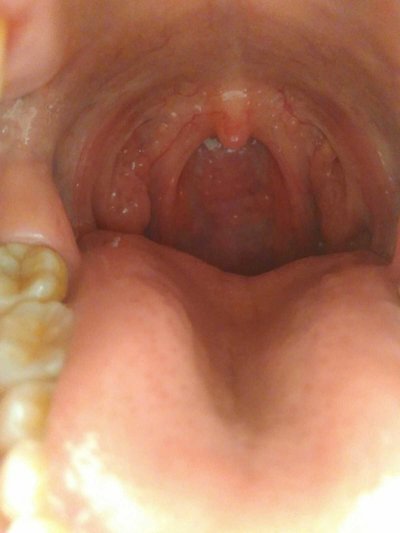

After the cough is almost cured, all the symptoms will suddenly disappear, and slowly find that the mouth sputum is less and less, and the cough time is shorter and shorter. Through such symptoms, we can judge whether the cough has improved. If it is improved, the mouth sputum will disappear, and there is no sputum when coughing. If some people have chest tightness during coughing, if they don't have it at this time, it means that their condition is about to improve.

From the clinical data, if it is a cough caused by a cold, then the decrease of cough frequency means that cough begins to improve; If it is a cough caused by upper respiratory tract infection, when people review their blood routine, if the white blood cell count gradually drops to the normal level, it also means that the cough has improved. For patients with cough and phlegm, when the disease improves in the later stage, they will feel that the sputum in the throat is significantly reduced, and the cough frequency of patients will be reduced. Of course, the patient's mental state and eating situation will be much better than before.